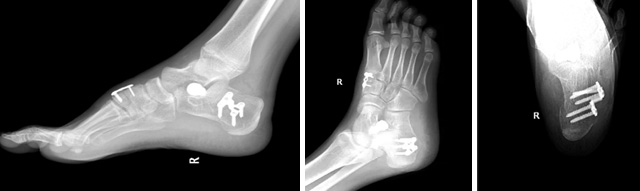

圖為患者扁平足術(shù)后影像資料

但該復(fù)雜僵硬性的扁平足單純給予副舟骨切除或距下關(guān)節(jié)制動(dòng)器置入不能糾正足弓。根據(jù)病情,小兒骨科對該復(fù)雜僵硬性扁平足患者進(jìn)行了右側(cè)扁平足跟骨內(nèi)移截骨鋼板固定,距下關(guān)節(jié)制動(dòng)器置入,腓長肌松解、肌腱固定,內(nèi)側(cè)楔骨截骨植骨鋼板固定等多處復(fù)雜性手術(shù)治療,手術(shù)歷經(jīng)1.5小時(shí),圓滿順利完成。

術(shù)后小兒骨科按照術(shù)前制定的護(hù)理及康復(fù)方案,從術(shù)后傷口護(hù)理、體位護(hù)理、下床訓(xùn)練、扶拐行走訓(xùn)練等各方面指導(dǎo)患者進(jìn)行康復(fù),治療效果滿意。這是玉溪市中醫(yī)醫(yī)院獨(dú)立完成的第一例復(fù)雜僵硬性扁平足手術(shù),標(biāo)志著我院治療青少年扁平足邁上了一個(gè)新的階段。